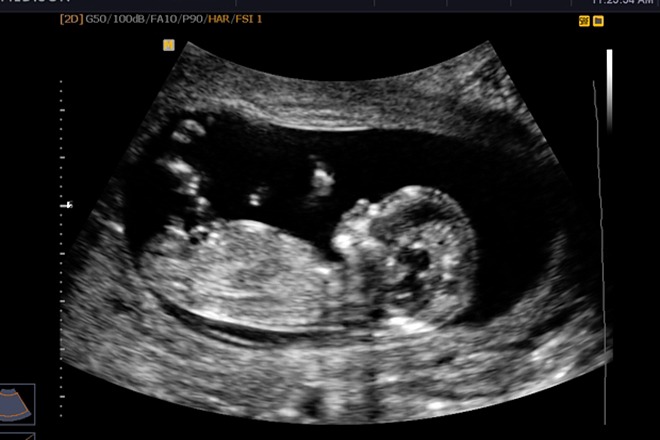

Thai nhi 12 tuần tuổi là thời điểm thích hợp để mẹ thực hiện siêu âm và kiểm tra một số chỉ số sức khỏe của con. Tại thời điểm này, thai nhi đã phát triển cơ bản đầy đủ về các chức năng của mọi hệ cơ quan, bắt đầu hình thành các giác quan, hệ cơ và các bộ phận của cơ thể. Hình ảnh thai 12 tuần cũng có thể giúp mẹ phát hiện những thay đổi bất thường của thai nhi nếu có để phòng ngừa dị tật bẩm sinh.

Bên cạnh việc siêu âm để theo dõi quá trình phát triển của bé, nhiều gia đình còn thực hiện siêu âm để giải đáp thắc mắc 12 tuần biết trai hay gái chưa. Nhờ sự phát triển trong cấu trúc cơ quan sinh dục với những chuyển biến rõ rệt nên hình ảnh siêu âm bé trai 12 tuần hay bé gái có thể giúp bác sĩ xác định giới tính thai nhi nhưng chưa thể chính xác hoàn toàn.